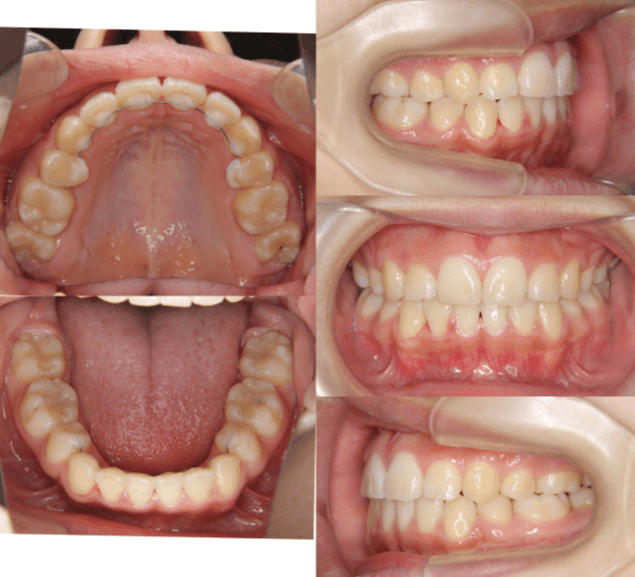

| 年齢・性別 | 11歳1ヶ月の女性 |

|---|---|

| 主訴 | 口元の突出感と歯並びが気になり、将来的な咬合状態を整える目的で来院された患者様です。 |

| 治療期間・回数 | 2年6ヶ月・25回 |

| 費用 | 720,000円 |